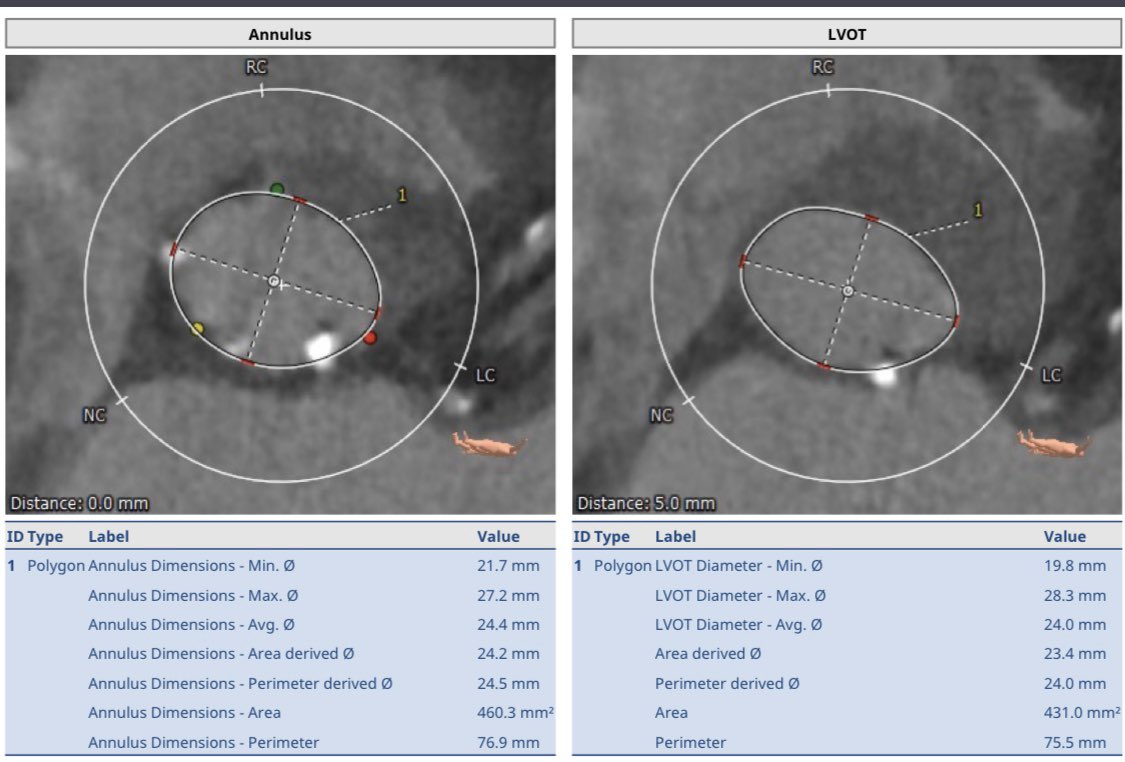

Our first #Sapien3Ultra #TAVR on the @Edwards_TAVR Commander system @MountSinaiNYC @MountSinaiHeart. Annular/LVOT Ca no PVL! Outstanding team! @KHERA_MD Samin Sharma, Annapoorna Kini, Stam Lerakis.